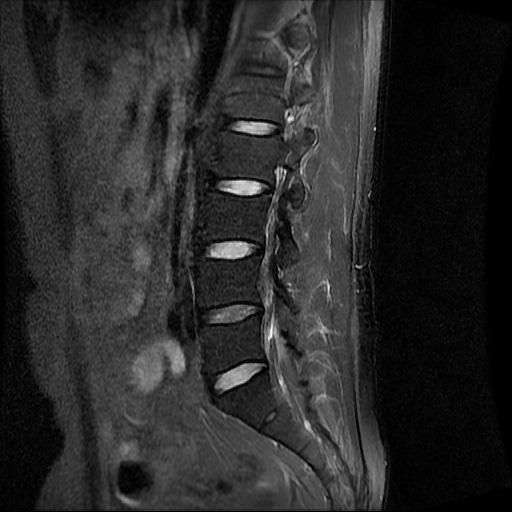

허리 MRI 디스크 상태 분석 부탁드립니다

건협에서는 관리해야 된다는데 디스크 협착이나 팽윤 등이 있는 상태인지 궁금합니다.

우선 현재로썬 사진만으론 판단을 하기에 제한이 되지만 사진상 디스크 상태는 심해보이지 않습니다.

요추부위의 하부 에서 약간의 팽윤이나 돌출로 의심해볼수 있는 정도이지만, 정확한 상태는 관련 전문의에게 진료시 문의를 하시는 것을 추천드립니다.